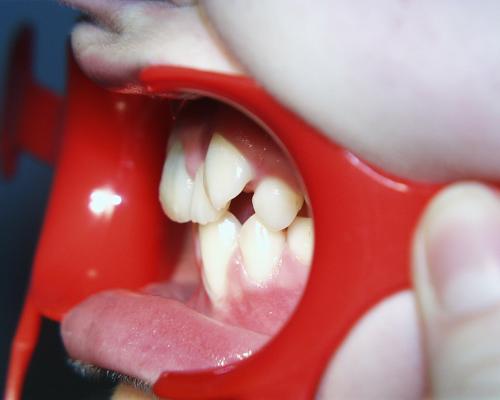

Vor der Behandlung

Fallbeispiel 7 ist ein besonders komplexer Fall. Die oberen mittleren Schneidezähne waren durch Stürze so stark vorgeschädigt, daß sie längerfristig nicht mehr erhalten werden konnten. Im Unterkiefer fehlten die zweiten (bleibenden) kleinen Backenzähne, die zweiten Milchbackenzähne standen daher noch im Kiefer. Es wurde beschlossen, die nicht erhaltungsfähigen oberen Schneidezähne und ausgleichend die beiden noch im Mund befindlichen Milchbackenzähne im Unterkiefer zu entfernen. Im Oberkiefer sollten die seitlichen Schneidezähne an Stelle der mittleren Schneidezähne bewegt und im Unterkiefer ein Lückenschluß ausgeführt werden.